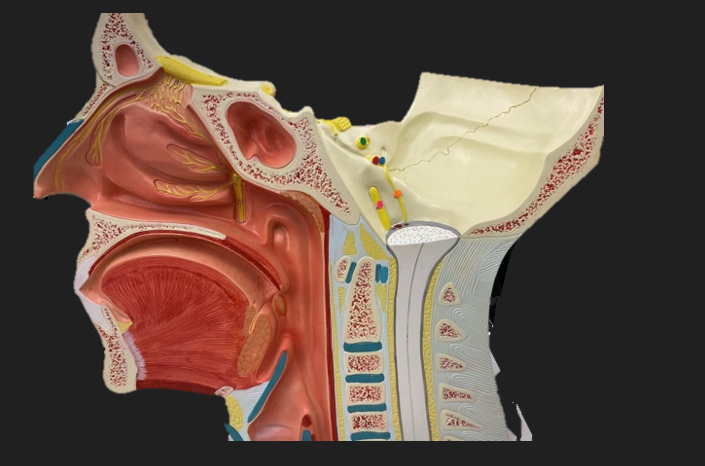

green dot

spinal nerve

orange dot

ventral root

pink dot

dorsal root

blue dot

dorsal root ganglion

red dot

dorsal ramus

yellow dot

ventral ramus

purple dot

anterior median fissure